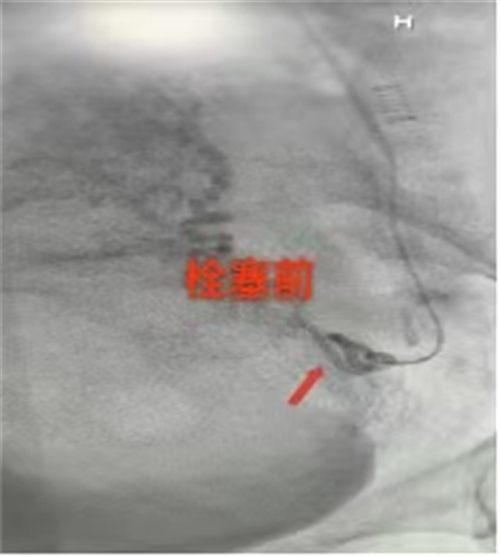

此次手术中,胸外血管外科医生团队借助DSA血管造影机(相当于“血管放大镜”),精准定位出血的子宫动脉,1小时40分钟便完成栓塞,“血止住了!”当这句话传来,守在门外的家属终于红了眼眶。术后24小时李女士就能下床,48小时各项指标恢复正常——对比传统开腹手术,介入术创伤小、恢复快,尤其适合急危重症患者。